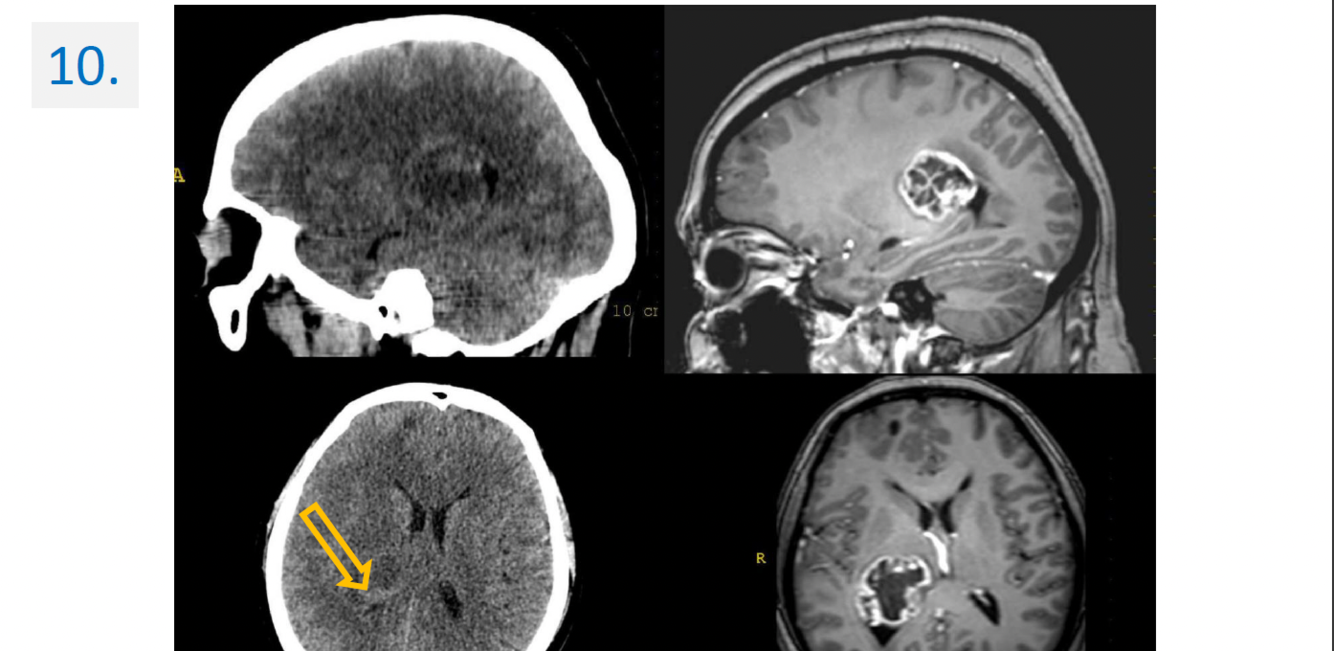

10.